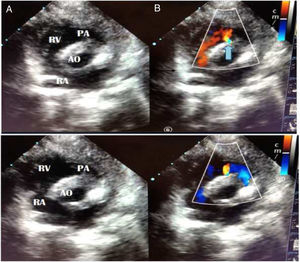

We present a case of a 6-month-old male infant who underwent intracardiac repair for Tetralogy of Fallot (TOF). He was operated by total repair approach with pulmonary valve preservation and after surgery he was shifted to Intensive Unit Care. Informed consents for surgery and publication were provided in accordance with national legislation. In an ultrasound routine check-up during the immediate postsurgical period, a constant pulsatile flow in the interventricular septum which reached the right ventricular outflow tract was detected, compatible with a coronary artery fistula (CAF) from the left coronary artery to the right ventricle (RV) (Fig. 1, Video 1.)

Short axis projection in sonography. It shows continuous flow in diastole (A) and systole (B). The blue arrow marks the fistula location. Its origins appears to be in the interventricular septum and it reaches the right ventricle infundibulum. RA, right auricle; RV, right ventricle. AO, aorta; PA, pulmonary artery.